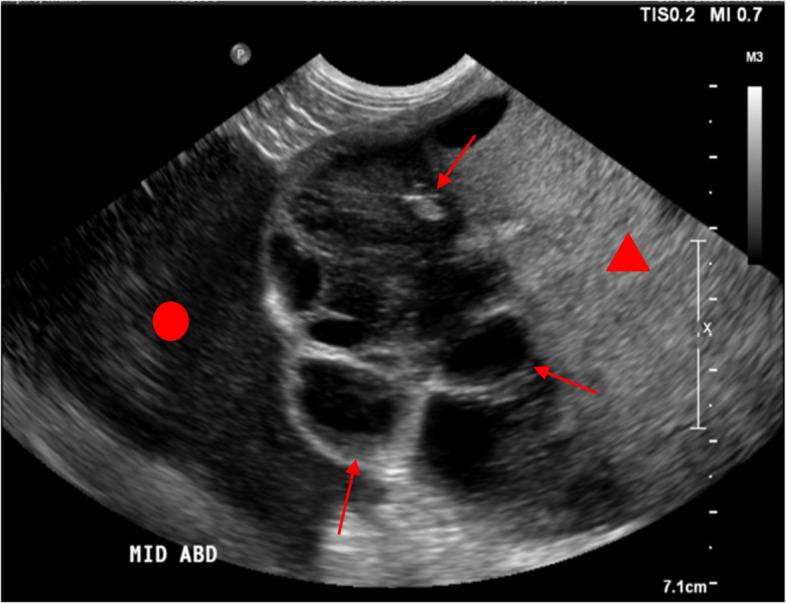

Gastrointestinal stromal tumor (GIST) presenting as a multilocular cystic intra-abdominal mass in a dog.

A ten-year-old, male-entire Maltese terrier mix breed dog presented with a large cystic mural mass of the duoedenum and orad jejunum. Histopathology and positive immunohistochemical staining with CD117 confirmed a diagnosis of GIST. No evidence of metastasis was detected on routine staging with abdominal sonography and thoracic radiography at the time of diagnosis. Surgical resection was performed and toceranib therapy was initiated post-operatively. Metastasis was documented 251 days after surgery on computed tomography. Due to clinical deterioration, the patient was humanely euthanised 370 days after surgical excision.

There are few differential diagnoses for large multilocular cystic intra-abdominal masses in dogs. This case presents a previously undescribed presentation of gastrointestinal stromal tumor in the dog as a predominantly multilocular cystic mass. It remains unclear if the cystic form of GIST may represent a favorable prognosis in dogs.